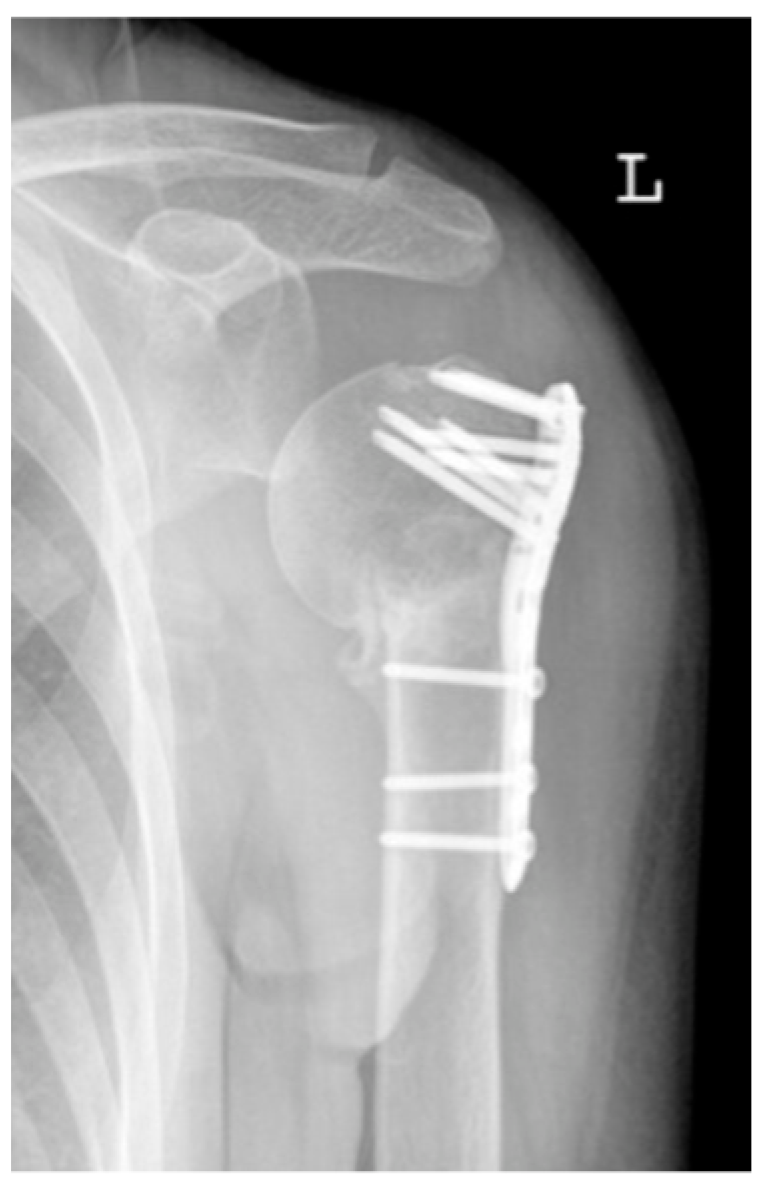

| 2b | ![]() | Complication Type 2b is limited to displacement of the greater tuberosity, lesser tuberosity, or both tuberosities. |